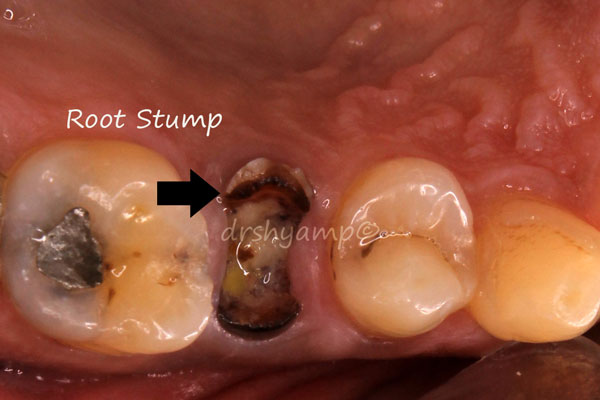

immediate dental implant

-

immediate dental implant

-

immediate dental implant